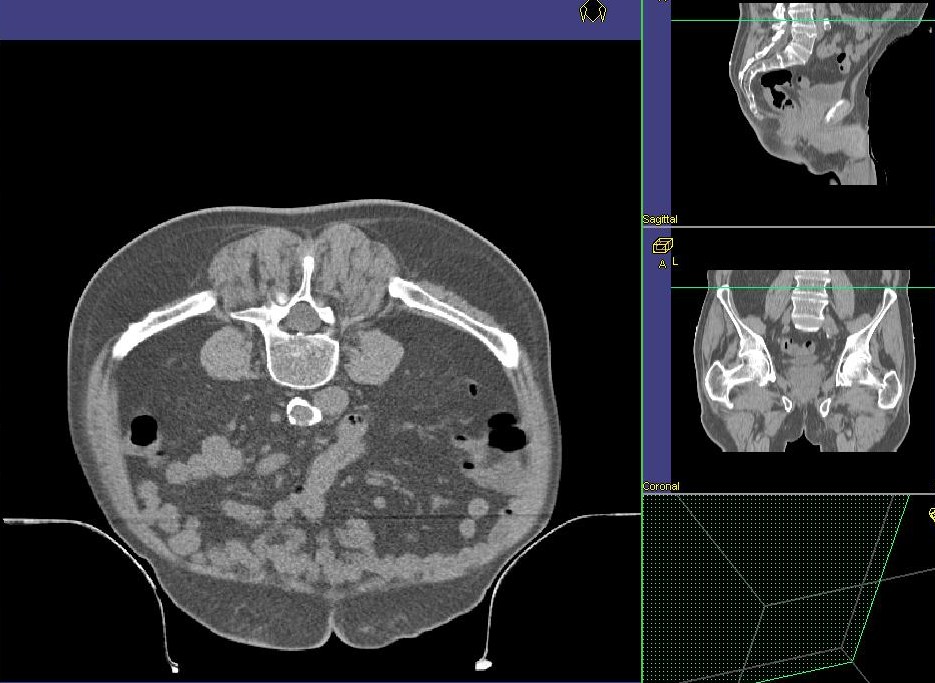

Belly - Board Durch die Bauchlage auf dem Belly - Board rutscht der Bauch in die Kuhle. Der Dünndarm wird größtenteils aus dem kleinen Becken entfernt und so geschont.